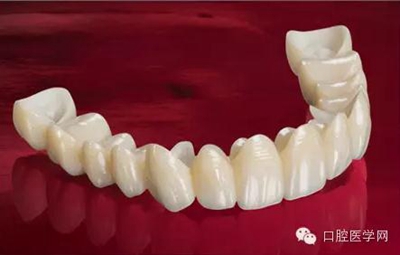

做完根管治療以后的牙齒,強度是有下降的,因為之前的齲壞,以及我們治療時為了讓器械能夠順利的進入根管內(nèi)部,要磨除一些牙體組織。為了防止牙齒因為自身強度下降而折斷,我們要給這個牙做一個全冠修復,有時候在做冠之前還要在根管里放一個樁進行加固。